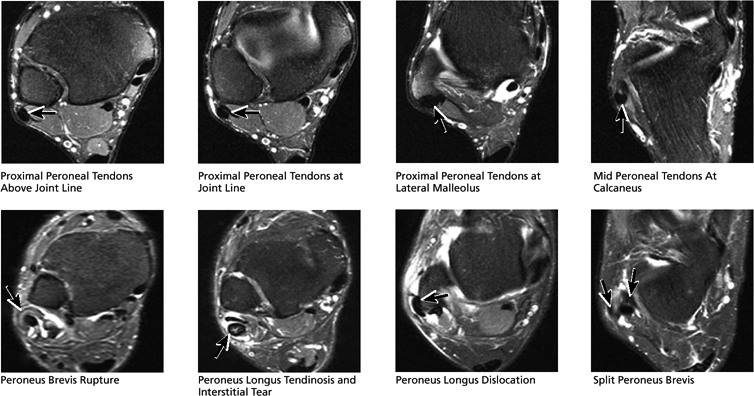

FIGURE 5.51 Lateral Tendons.